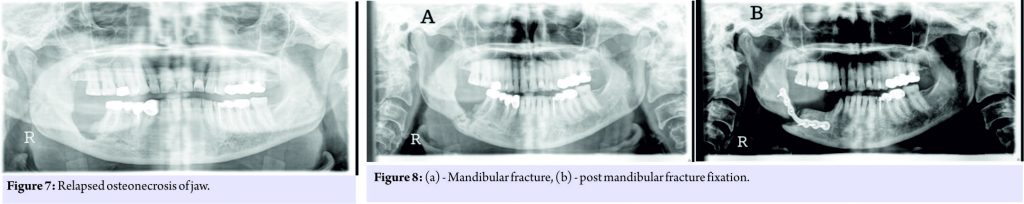

The knee replacement was unrelated to the sub-trochanteric fracture. For the subtrochanteric fracture of femur, regular follow-ups were done postoperatively with serial X-rays. Blood investigations were done, and serum calcium was 9.5mg/dl, and serum Vitamin D3 was 20ng/ml which was optimized with 6,00,000 IU of intramuscular Vitamin D3 and maintained by oral Vitamin D3 medications. At 3 months, the fracture was in delayed union (Fig. 5),and hence, the patient was started on injection Teriparatide 20mcg subcutaneous for a period of 18 months. The patient was kept non-weight bearing. The 6 months X-ray showed further progression in fracture healing (Fig. 6),and the patient was allowed partial weight bearing. In October 2013, 10 months after stopping Alendronate, she again came with the complaint of pain in the right side of the jaw; X-rays showed relapse of ONJ (Fig. 7) sequestrectomy was done on the right mandible. In February 2014, 13 months after stopping Alendronate, the patient came with the increased pain of the right mandible and was diagnosed as a fracture of the right mandible; the fracture was operated on and fixed with a plate in February 2014 (Fig.8).